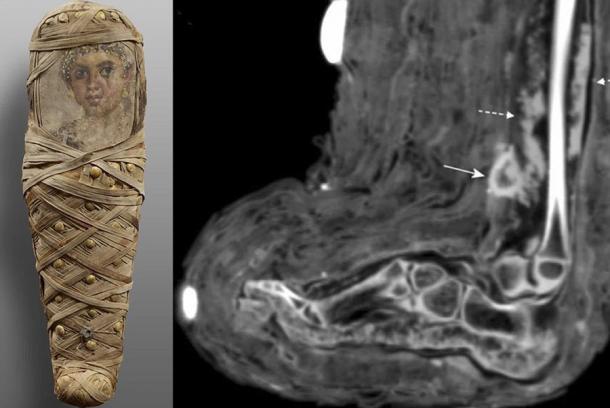

Scan of Child Mummy Reveals Bandages and Pus-Filled Wound

On the left, photograph of ancient Egyptian child mummy from Tomb of Aline, discovered in Hawara. On the right, CT scan of soft tissue infection in the lower leg, showing a mass consistent with dried pus. Source: Panzer et. al / International Journal of Paleopathology

During a computed tomography (CT) scan of a child mummy belonging to a youngster who lived in ancient Egypt, archaeologists found something unique and most unexpected. The imagery they obtained revealed evidence of a pus-filled and bandaged wound on her right lower leg, indicating the small girl had died from some type of infection.